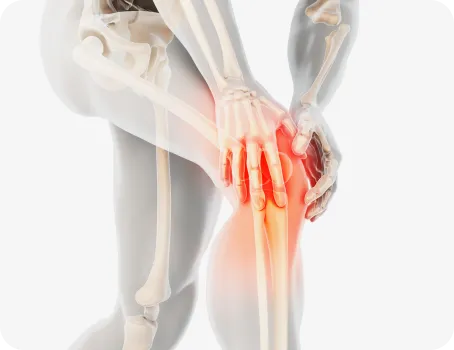

무릎

무릎의 변형을 발질환에 많은 영향을 미칩니다.

O 다리나 X 다리 , 무릎이 뒤로 밀려난 슬관절과신전 패턴 등은 보행패턴을 망가뜨리고 정상적인 보행을 방해하여 발질환을 만성화시키는 주 원인이 됩니다.